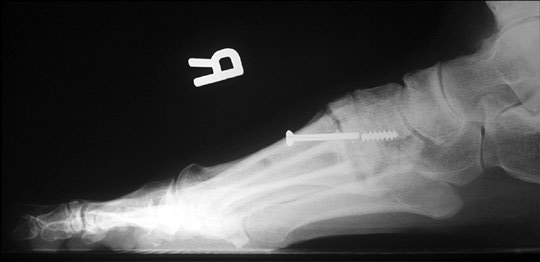

Broken:

Broken screw following Lapidus procedure. Cancellous screws, especially the thinner ones, usually break at the junction of the shank and the threaded portion. Therefore, this probably represents at least a delayed union if not a nonunion. However, if correct position is maintained, as in this case, and the surgical site is painless, it may be considered a satisfactory result.